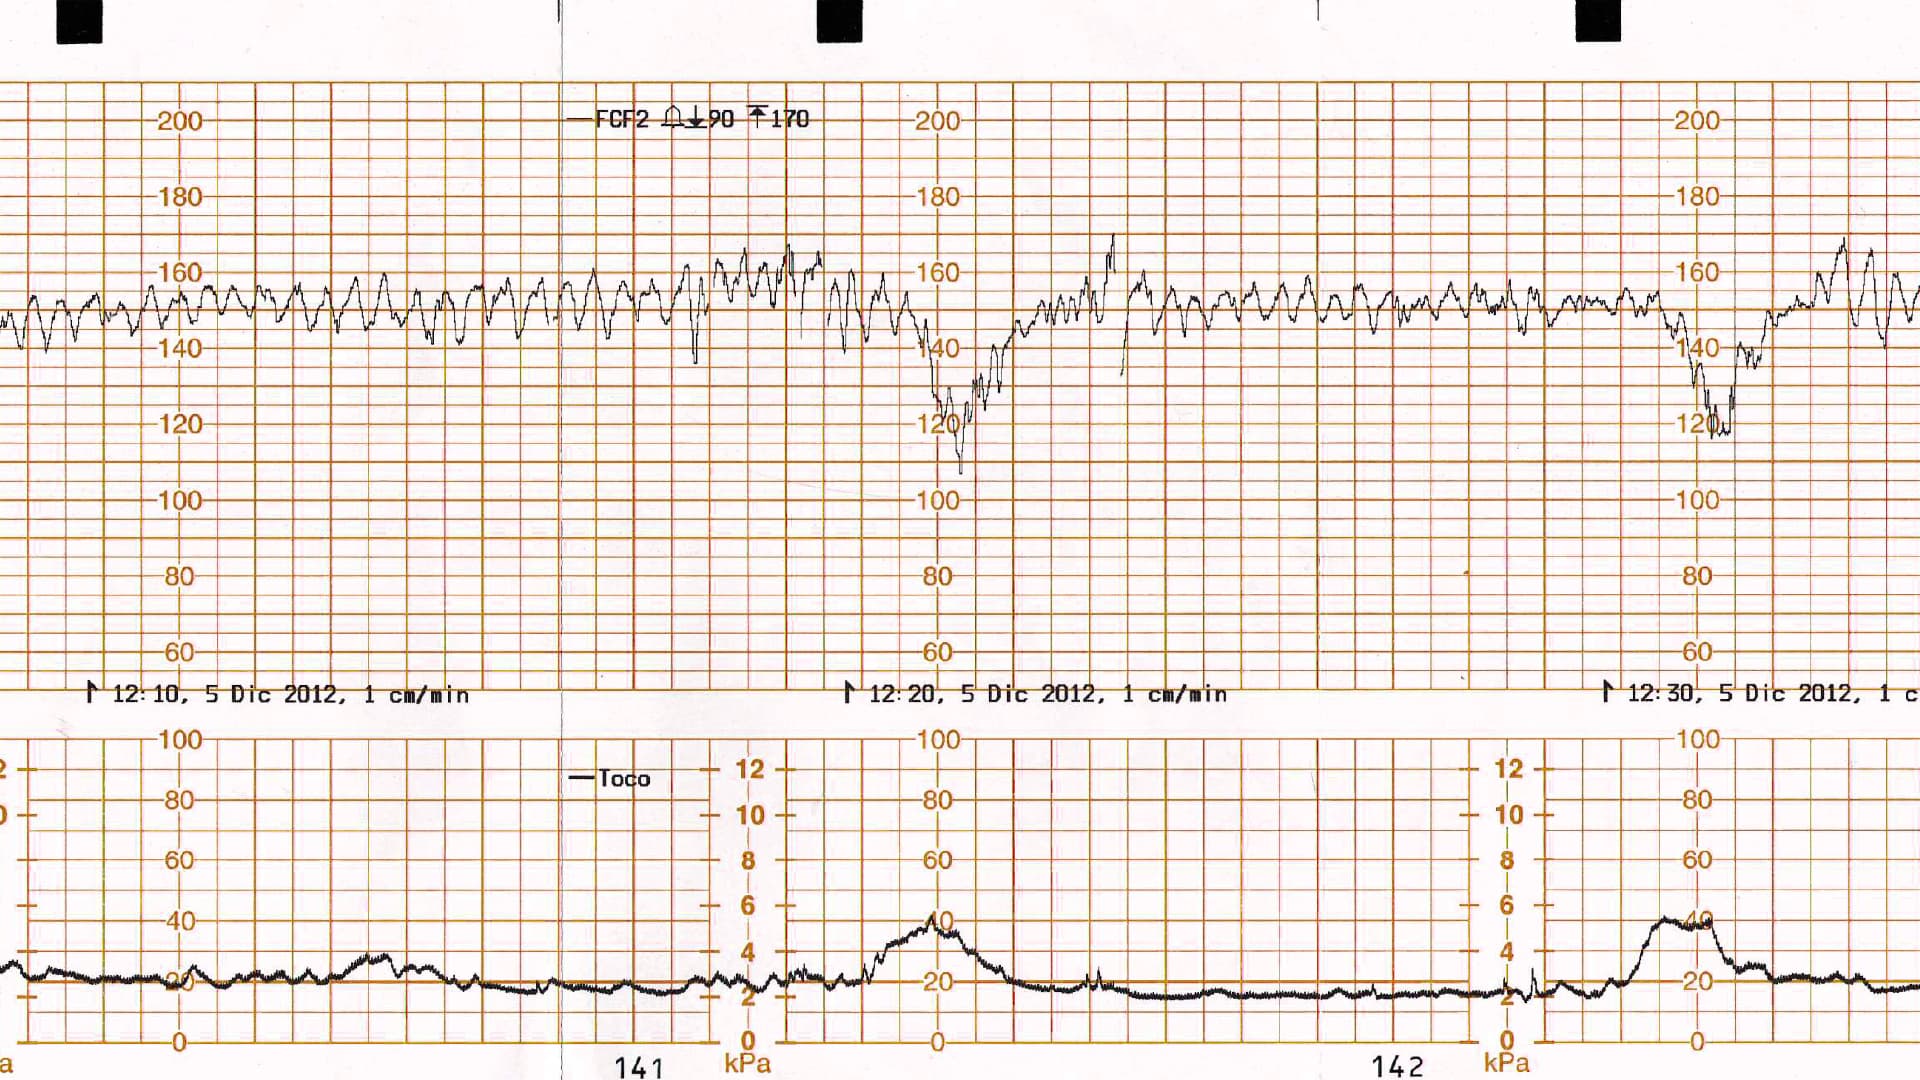

Suplementación con oxígeno en el escenario de un registro cardiotocográfico categoría II o III

La suplementación con oxígeno es una práctica común para la resucitación intrauterina en el contexto de un registro cardiotocográfico categoría II o III, a pesar de la poca evidencia que respalde su uso.

En un estudio reciente que involucró la suplementación de oxígeno anteparto, se concluyó que la suplementación con oxígeno no resolvió los registros cardiotocográficos categoría II o III.

Basados en esta nueva evidencia, el uso rutinario de suplementación con oxígeno no se recomienda en mujeres con saturación normal de oxígeno, para resucitación fetal intrauterina.